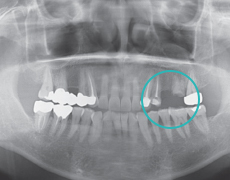

ETAPA 2

ProcedimientoPrimario (Instalación del implante)Posicionamiento de implante en el sitio.

ETAPA 3

Procedimiento Secundario, (Oseointegración y conección de pilar)Conexión del implante y pilart.